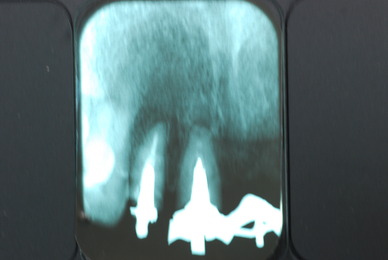

必ずばい菌が侵入しないようにしてばい菌である虫歯を除去します。

銀歯の下はばい菌だらけです。こういうのはよくあります。取り残しですね。![treatment_05[1]](https://livedoor.blogimg.jp/netdental/imgs/3/a/3ad019d0-s.jpg)